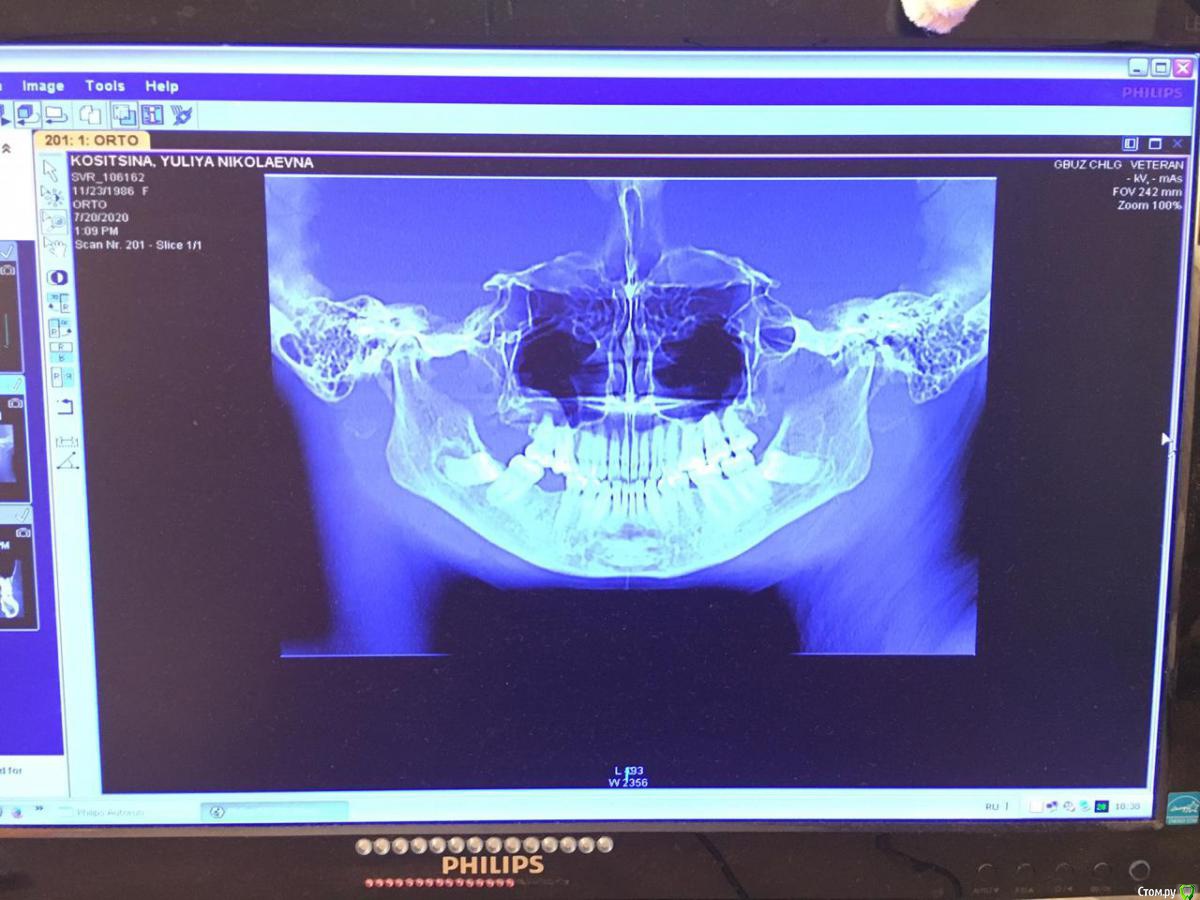

Юлия2386 Опубликовано 30 июля, 2020 Поделиться Опубликовано 30 июля, 2020 Добрый день, уважаемые врачи! Прошу вашей помощи, так как уже замучалась я конкретно. У меня уже 9 месяцев боли в правой стороне лица давящего характера. Давит на лоб, глаз, иногда висок. С декабря 2019 выявили фронтит-гайморит, проходила лечение у Лора и ещё невролога. Окончательного результата по выздоровлению за это время не достигнуто. Видимо это одномерный гайморит, так как постоянно какое-то воспаление формировалось у зубов 1.6;1.7;1.8. Многие стоматологи не видят проблем в зубе 1.6. Посоветовали удалить зуб 1.8 так как там был глубокий десневого карман. Удалила, а воспаление разрослось ещё больше (после удаления поцарапала щеку зубом 1.7, возможно из-за этого разрослось воспаление?!) После удаления прошёл месяц, а картина сейчас такая https://yadi.sk/d/ziceEN_jVZ9IkwВ итоге последний врач сказал, что все-таки проблема идёт от зуба 1.6, так как не запломбирован один канал, но из-за того что у зуба входят корни в гайморовых пазуху, лечить его не видет смысла, порекомендовал его удалить и через лунку вычиститься всю слизь, но он этим не занимается. Теперь я замешательстве и не знаю, что мне с этим делать, а самое ужасное, что глаз от этого болит( Уважаемые доктора, очень прошу вашей помощи, выскажите пожалуйста ваше мнение и может посоветуете к кому с этим можно обратиться в Москве. Ссылка на комментарий

wladdX Опубликовано 31 июля, 2020 Поделиться Опубликовано 31 июля, 2020 Представленная спиральная КТ не позволяет детально рассмотреть корневые каналы зубов и тп, чтобы получить какое-то внятное суждение.На уровне зубов 18, 17 и 16 есть локальное утолщение слизистой оболочки синуса и это всё, что из этого исследования можно выяснить. Адекватность обтурации корневых каналов зуба 16 оценить не представляется возможным (по крайней мере в моём понимании).Я бы порекомендовал сделать КЛКТ (конусно-лучевую компьютерную томографию), используемую в стоматологии. Ссылка на комментарий